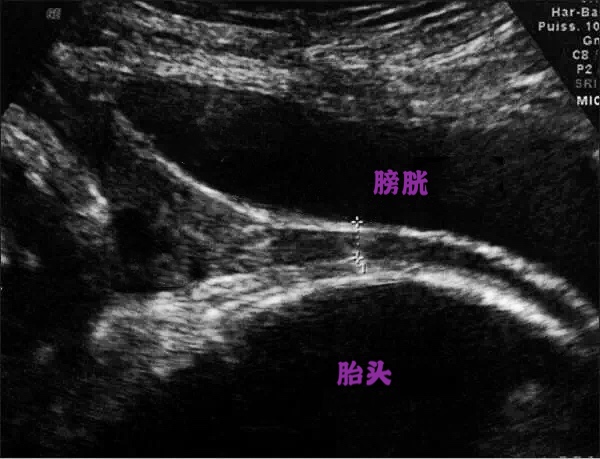

4、中晚孕期疑前壁胎盘粘连孕妇

中晚孕时特别是第一胎有剖宫产的孕妇,需要通过超声来视察胎盘粘连及其分度,中晚孕的孕妇因为有胎儿对膀胱的压迫,孕妇常会感到尿频导致更不能憋尿过多,怀疑胎盘粘连的孕妇只需要有憋尿的感觉即可,喝250ml温开水后半小时可检查。